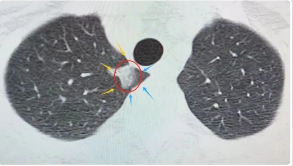

50岁的张女士(化名)是一名慢性肾衰竭患者,多年来坚持规律透析,一次常规检查时发现了肺结节,由于病灶比较小,当时并未进一步处理。一年后再次复查时,张女士的肺结节体积明显增大,从CT影像可见:右肺上叶尖端混合结节大小约为17x11mm,形态不规则,边缘有毛刺,恶性可能性较大。

(影像检查资料)